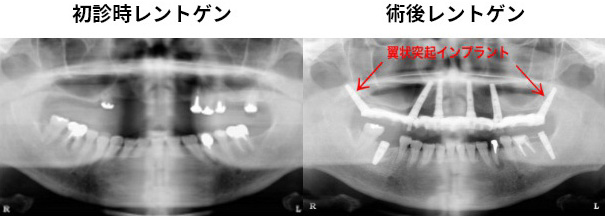

翼状突起インプラントの症例

60歳代 女性 インプラント(上顎6本)

術式:翼突口蓋窩(上顎結節・翼状突起部)を利用したノーベルガイド、オール・オン6、即時負荷

| インプラント | 60歳代 女性 |

| 主訴 |

残根上に総義歯を装着しているが、会話や食事が不自由である。 |

| 治療内容 |

【上顎】 |

| 治療結果 |

メンテナンスに継続して来院頂き、手術後15年以上経過していますが、インプラントの状態は良好です。 |

| 治療期間 | 7ヶ月 |

| 治療費用 | 上顎 300万円(税込) |

| リスク | 術後の痛み、腫れ。 |

術後15年以上が経過していますが、インプラントの状態は良好です。